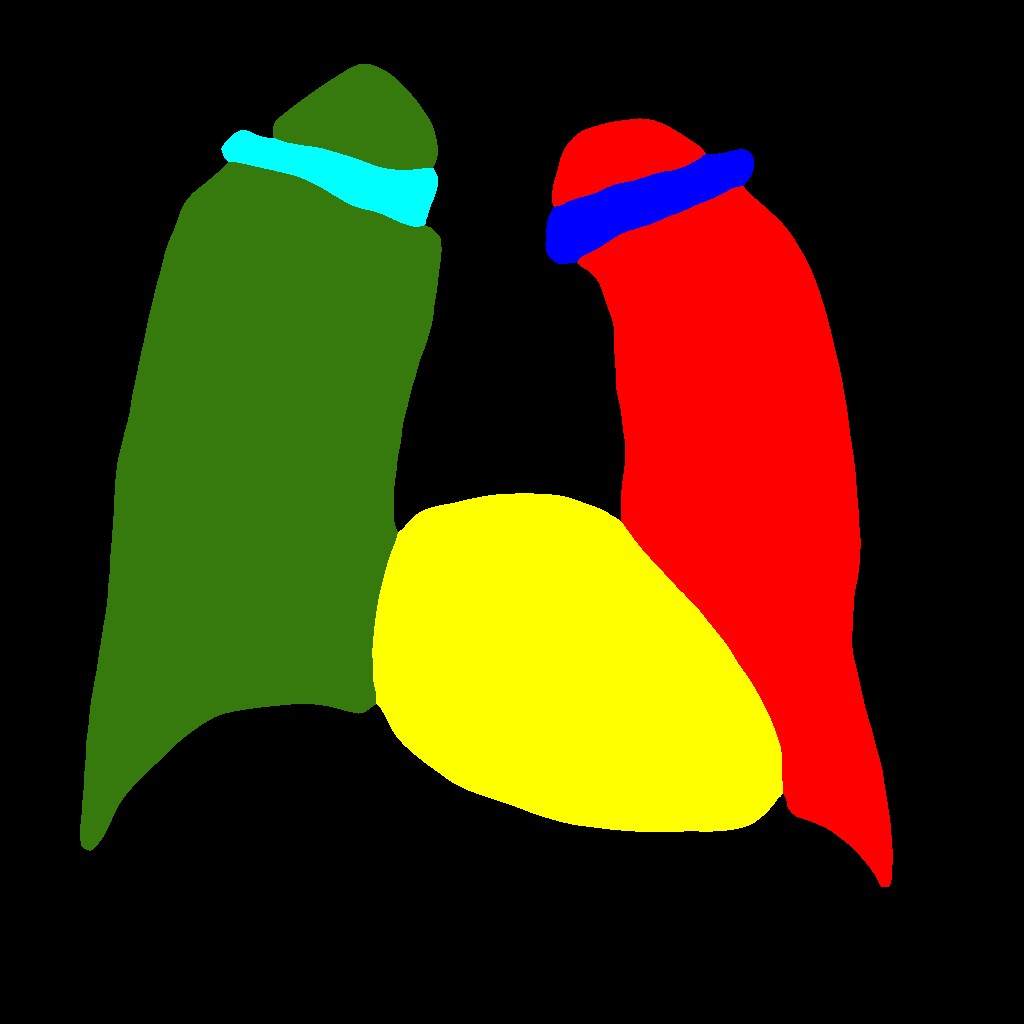

This baseline approach consists in stacking X–ray images and labels into two different channels, which are simultaneously fed into the PGGAN. Therefore, the PGGAN is trained to generate pairs composed by an X–ray image and its corresponding label (see Figure 1).